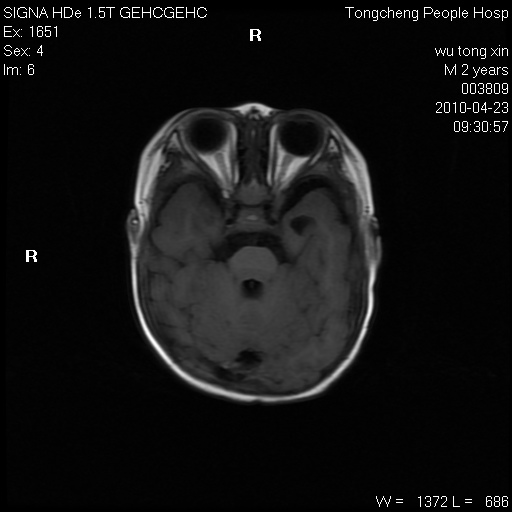

以下是引用赵物学在2010-4-25 12:43:00的发言:[br]巨脑回[br]侧脑室后角低密度影考虑hie或肾上腺脑白质营养不良?[br][br][本贴已被 赵物学 于 2010-4-25 12:51:28 修改过]

以下是引用gaoxiao在2010-4-25 16:54:00的发言:[br]巨脑回畸形。脑白质髓鞘化不良

以下是引用pujunzhi在2010-4-25 21:35:00的发言:[br]考虑 1双侧大脑皮质发育不良 2轻度脑积水 3双侧脑室后角旁片状长t1长t2信号,需继续观察,因为正常小儿此处脑白质的髓鞘化时间可以延迟到4-6岁,才显示正常。